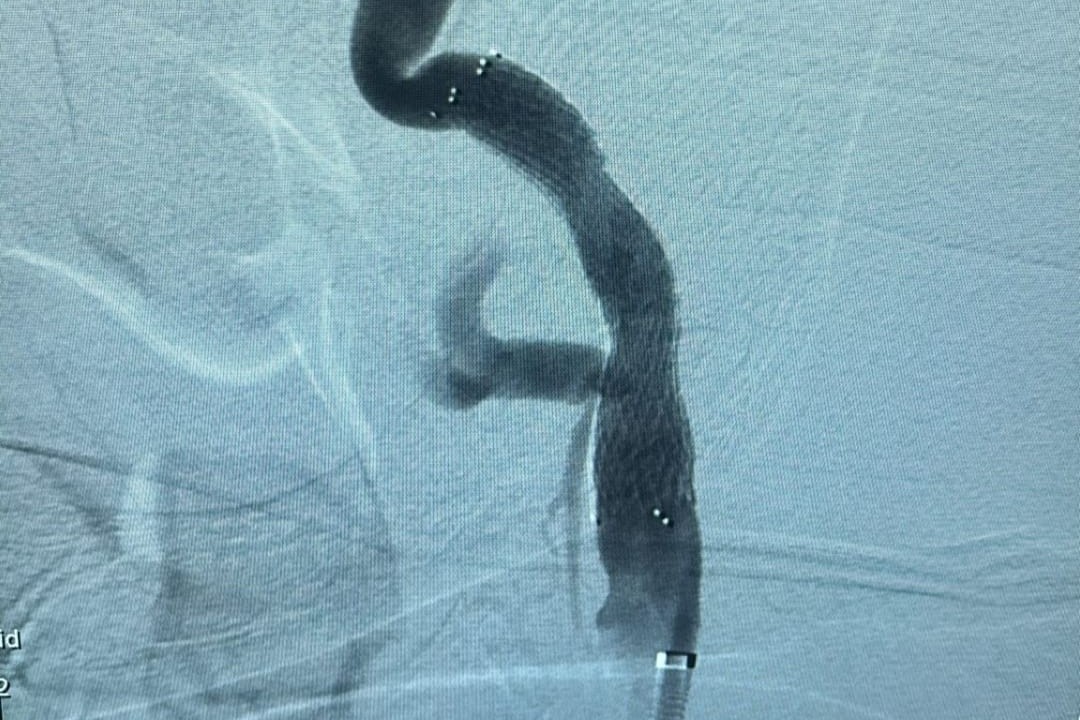

Boynun her iki yanında yer alan şah damarlarında zamanla kolesterol, kireçlenme gibi nedenlerle oluşan plaklar, damarda daralmaya neden olabiliyor. Bu durum tedavi edilmediğinde beyin felci (inme) gibi ciddi sonuçlara yol açabiliyor. Girişimsel Radyoloji Ünitesi’nde uygulanan yöntemde, darlık tespit edilen damara özel bir balon yardımıyla müdahale ediliyor ve ardından stent adı verilen ince metal bir kafes yerleştirilerek damarın açık kalması sağlanıyor. Bu sayede, kan akışı normale dönüyor ve felç riski önemli ölçüde azaltılıyor.

Anjiyografi ünitesinde, ameliyatsız olarak uygulanan bu işlem sayesinde hastalar kısa sürede iyileşme gösteriyor. Şu ana kadar tedavi edilen hastalarda olumlu sonuçlar alınırken, bu uygulama rutin bir işlem haline gelmiş durumda.